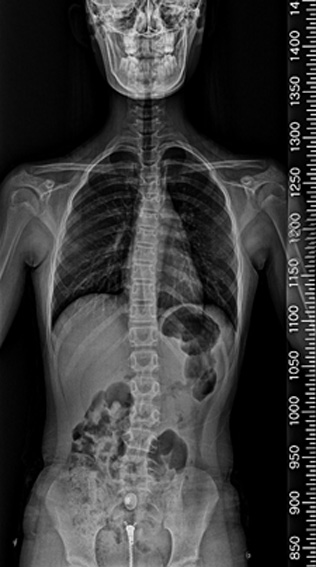

척추 측만증은 80%가 사춘기 때 발생하며, 사춘기 여아의 10~14%, 사춘기 남아의 5%에서 나타나는 것으로 알려져 있습니다. 성조숙증이 있는 아이들은 더 어린 나이에 급성장이 온 것이기 때문에 척추 측만증이 생길 가능성이 더 높습니다. 성장호르몬 치료를 하는 경우에도 사춘기때처럼 급성장을 하기 때문에 척추 측만증이 생길 가능성이 더 높습니다. 물론 이는 약물 부장용이 아닌, 일종의 성장 부작용인 셈입니다. 척추 측만증은 심할수록, 골연령이 어릴수록, 그리고 역연령이 어릴수록 점점 더 심해질 가능성이 높으며, 따라서 가능하면 조기에 발견하여 치료하는 것이 좋습니다. (from Lonstein & Carlson) 이렇게 척추 측만증은 일종의 성장기 합병증으로 볼 수 있으며, 따라서 성장판이 닫칠 때까지 더 진행될 확률이 높고 대신 성장판이 닫치면 진행도 멈추게 됩니다.

더 어린 나이에 급성장이 온 것이기 때문에 척추 측만증 및 척추질환 등이 생길 가능성이 더 높습니다.

척추 측만증 : 앉아 있기가 힘이 들며 어깨 높이가 다른등 척추 부위 통증 및 걸음걸이, 자세등에 다양한 불편감 호소.